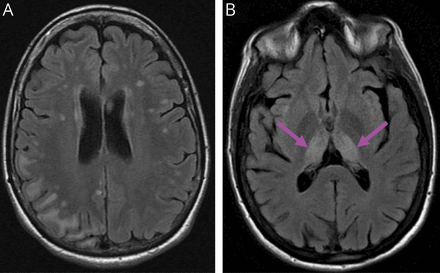

对于MD模拟物,WGS能够在更大的目标基因列表中检测变异,从而允许诊断和区分患有其他可治疗疾病的患者,从而对各自的疾病进行适当的护理和治疗,同时排除MD。3名患者被诊断为α-甲基酰基辅酶a消旋酶(AMACR)缺乏症。e1包括2姐妹(表1;B45和E19患者,表3,links.lww.com/WNL/C92),他们有癫痫、脑病和提示MD的中风样发作。随着AMACR缺陷的确认遗传诊断,他们接受了普里斯坦酸饮食限制的治疗40,41这导致症状改善。据报道,治疗前他们的大脑mri显示右侧顶枕皮质带或双侧丘脑T1高信号强度,提示诊断为MD (图6).此外,2名兄弟姐妹(表1;出现进行性眼外肌麻痹和近端肌无力的患者B42和B43(表3),发现在眼球中存在一种新的纯合剪接变异麝香基因(c.358 + 3 g > T;图4),随后用沙丁胺醇治疗。42

在我们的分析中,我们还考虑了神经肌肉疾病相关基因的变异,并确定了到我们诊所就诊的患有类似MD疾病的患者(例如,先天性肌无力和神经棘细胞增多症),尽管这些患者的肌肉活检异常和临床症状与MD诊断一致(表1).分子诊断的提供和MD模拟的确认导致了医疗管理的变化(表1),并告知他们将疾病遗传给后代的风险。此外,3例提示MELAS或Leigh综合征的神经系统表现(局灶性神经功能缺损、与脑MRI异常相关的癫痫发作)患者被确定为AMACR缺陷e1(图6,表3,links.lww.com/WNL/C92),证明WGS能够通过识别通过简单的饮食限制可以治疗的疾病来改变临床管理,41以及为具有治疗选择的MD表型提供诊断(表1).